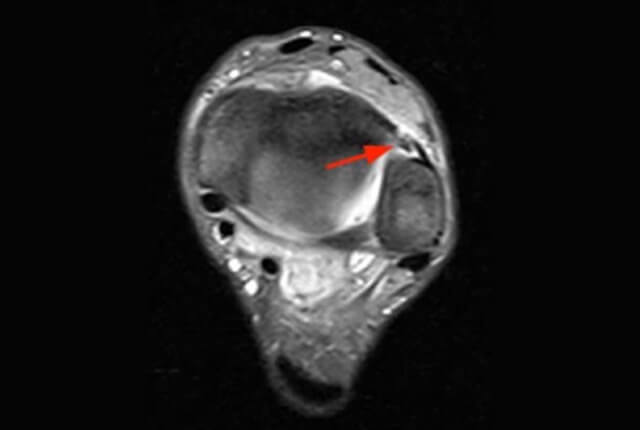

• MRIで靱帯損傷の部位と程度を確認します

MRI